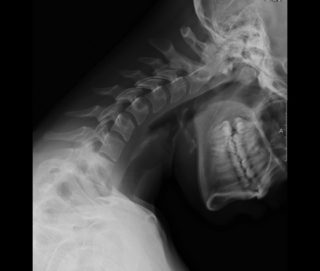

Рентгенография с функциональными пробами позволяет изучить все самые подвижные части позвонков. Процедура назначается для исследования патологической межпозвоночной подвижности или функционального блока.

Снимки шейного отдела, выполненные в условиях проведения функциональных тестов:

- диагностируют смешение вышележащих позвонков относительно нижележащих;

- устанавливают характер и степень изменения передней стенки позвоночного канала.

При рентгенографическом исследовании с функциональными пробами у врачей есть уникальная возможность изучить наиболее подвижные части шейных позвонков. Проводится с целью диагностирования патологической подвижности между позвонками или, наоборот, блокирование позвонков.

При выполнении функционального теста врачи получают результаты:

- видят смещение позвонков друг относительно друга;

- могут установить степень изменения стенки позвоночного канала спереди и установить характер этих отклонений.

Проведение рентгеновского исследования с функциональными пробами помогает выявить некоторые патологии на ранней стадии развития.

Например, информативным является исследование при наличии у пациента остеохондроза на ранней стадии. При диагностике заболевания уже можно принимать меры по остановке патологического процесса и лечения последствий деструктивных изменений.

В случае, когда при первичном визуальном осмотре и пальпации были выявлены наличие сильных болей в суставах или же чрезмерная подвижность и выпячивание позвонков, врач может назначить больному рентген шейного отдела позвоночного столба с функциональными пробами. Функциональной пробой называют дополнительные условия, которые создаются при изучении определенного органа для получения более информативного изображения и дальнейшей детальной диагностики.

Рентгенография шейного отдела позвоночника с функциональными пробами подразумевает выполнение снимка в состоянии полного сгибания шеи, а затем – полного ее разгибания. Такая двигательная активность позволяет выявить некоторые патологии суставов и позвоночника еще на начальных стадиях.